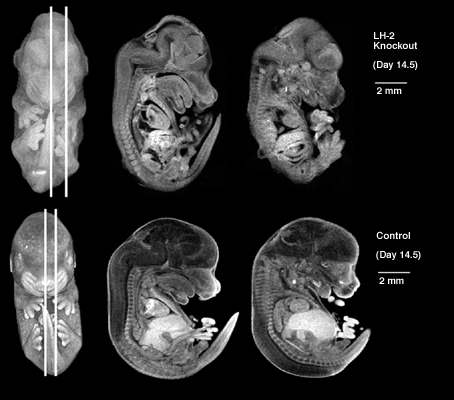

Sagittal views of LH-2 knockout embryos compared to normal control embryos. The LH-2 knock-outs were produced by F.D. Porter.

LH-2 Knockout mouse embryo image